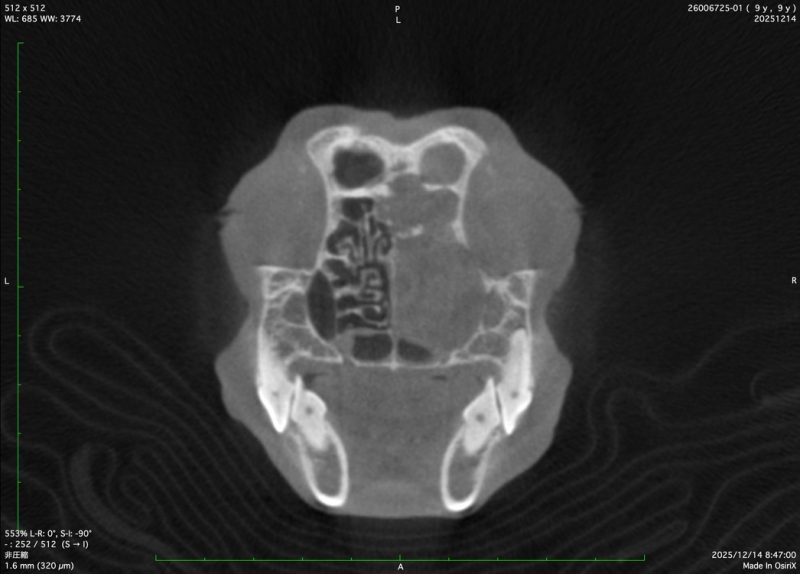

CT検査

2025年12月14日(日)

手術後約半年が経ちCT検査に病院に行きました。

CT検査の結果、残念ながら、癌が再発してました。

顔面の腫瘍はなかなか取りきれないそうです。

抗がん剤治療するか、再手術するか慎重に検討します。